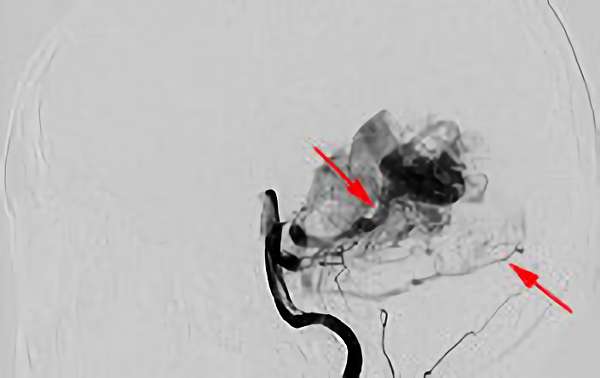

'24年8月

左前頭葉脳動静脈奇形

10代

秋田県の病院

No.1494 手術中